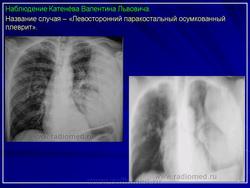

2. Осумкованный паракостальный плеврит.

Пристеночные (паракостальные) осумкованные плевриты являются результатом неполного рассасывания свободного экссудативного паракостального плеврита или транссудата, свои широким основанием прилежат к поверхности ребер.

В типичных случаях рентгенологическая картина пристеночных осумкований довольно характерна.

Они, скиалогически проявляясь синдромом «ограниченного затемнения», имеют форму теней, примыкающих широким плоским основанием к реберному краю.

Левосторонний паракостальный осумкованный плеврит.